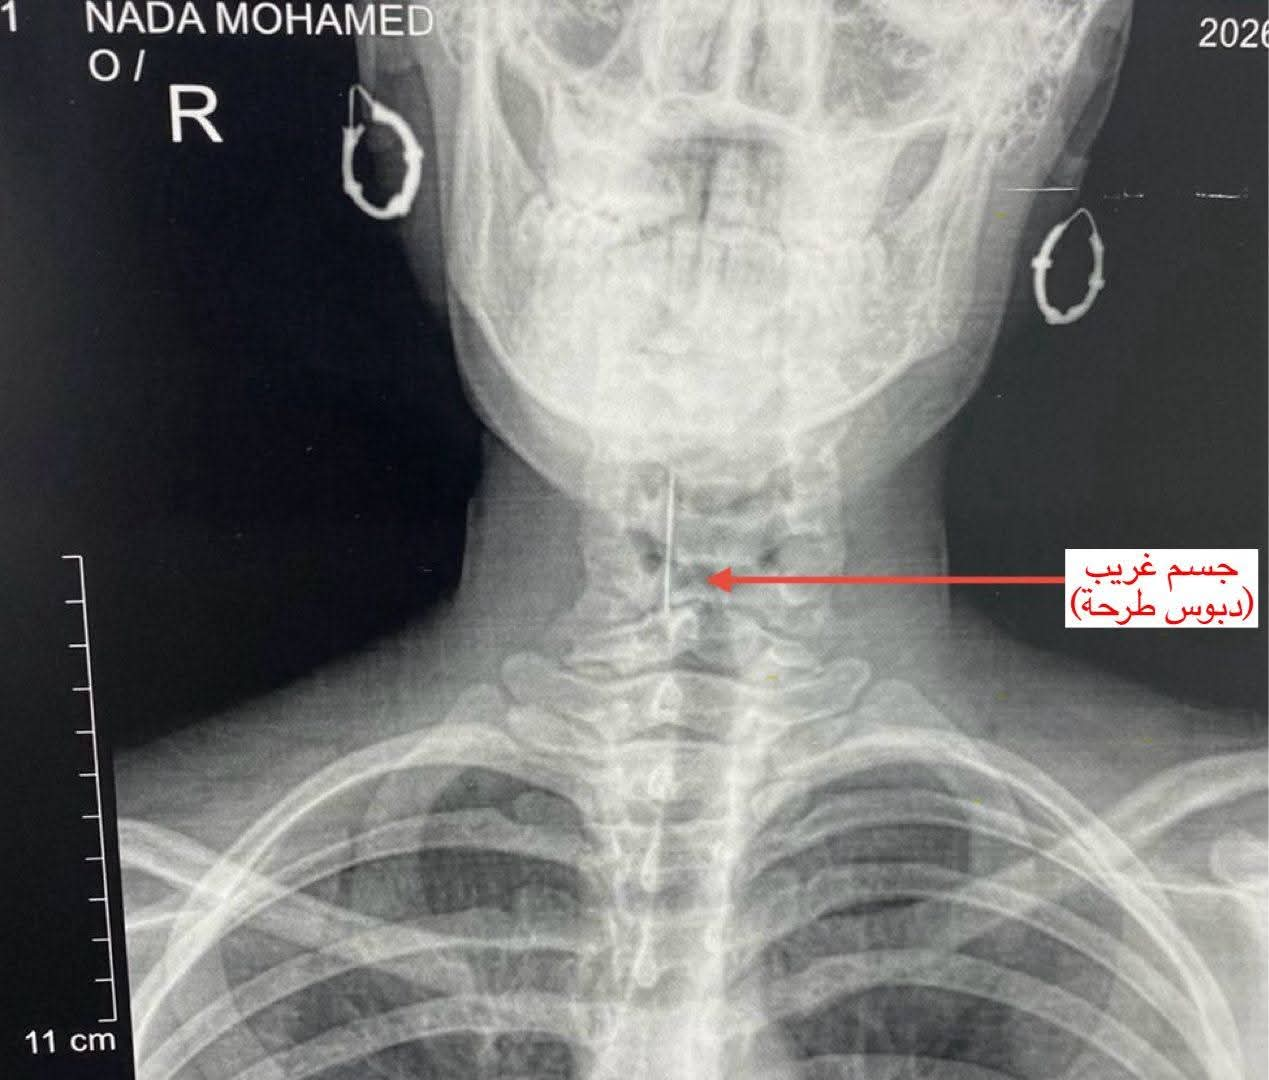

استقبل قسم الطوارئ بالمستشفى الفتاة وهي تعاني من آلام شديدة في الرقبة وصعوبة في التنفس. أجريت الفحوصات اللازمة والأشعة التي أكدت وجود الجسم الغريب في منطقة دقيقة بالمجرى التنفسي مما كان يشكل خطرًا على حياتها.